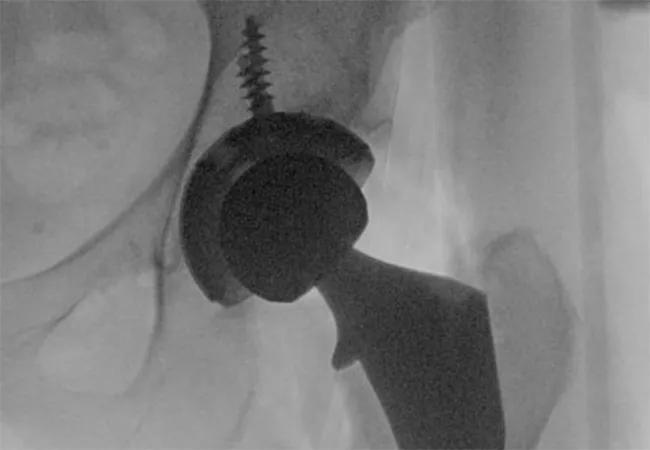

Total hip arthroplasty (THA) is a common procedure to treat osteoarthritis, osteonecrosis and even femoral neck fractures. The three main approaches are posterior (from the back), direct lateral (from the side) and direct anterior (from the front).

Within direct anterior THA, techniques can involve using a standard operating room table or a specialized orthopaedic table. Robotic assistance can be used to help in preparation and positioning of the acetabular component. When using a specialized orthopaedic table, fluoroscopy can help with preparation and positioning of the acetabular component as well as positioning of the femoral component and reproducing leg length and offset compared to the preoperative or contralateral hip.